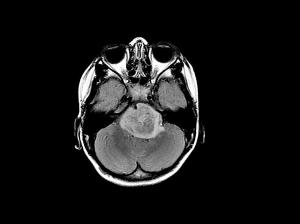

Scientists at Stanford Medicine discovered that you can halt aggressive brain cancers called high-grade gliomas by cutting off their supply of a signaling protein called neuroligin-3. Their research, which was funded by CIRM and the NIH, was published this week in the journal Nature.

The Stanford team, led by senior author Michelle Monje, had previously discovered that neuroligin-3 dramatically spurred the growth of glioma cells in the brains of mice. In their new study, the team found that removing neuroligin-3 from the brains of mice that were transplanted with human glioma cells prevented the cancer cells from spreading.

“We thought that when we put glioma cells into a mouse brain that was neuroligin-3 deficient, that might decrease tumor growth to some measurable extent. What we found was really startling to us: For several months, these brain tumors simply didn’t grow.”

The team is now exploring whether targeting neuroligin-3 will be an effective therapeutic treatment for gliomas. They tested two inhibitors of neuroligin-3 secretion and saw that both were effective in stunting glioma growth in mice.

Because blocking neuroligin-3 doesn’t kill glioma cells and gliomas eventually find ways to grow even in the absence of neuroligin-3, Monje is now hoping to develop a combination therapy with neuroligin-3 inhibitors that will cure patients of high-grade gliomas.

“We have a really clear path forward for therapy; we are in the process of working with the company that owns the clinically characterized compound in an effort to bring it to a clinical trial for brain tumor patients. We will have to attack these tumors from many different angles to cure them. Any measurable extension of life and improvement of quality of life is a real win for these patients.”